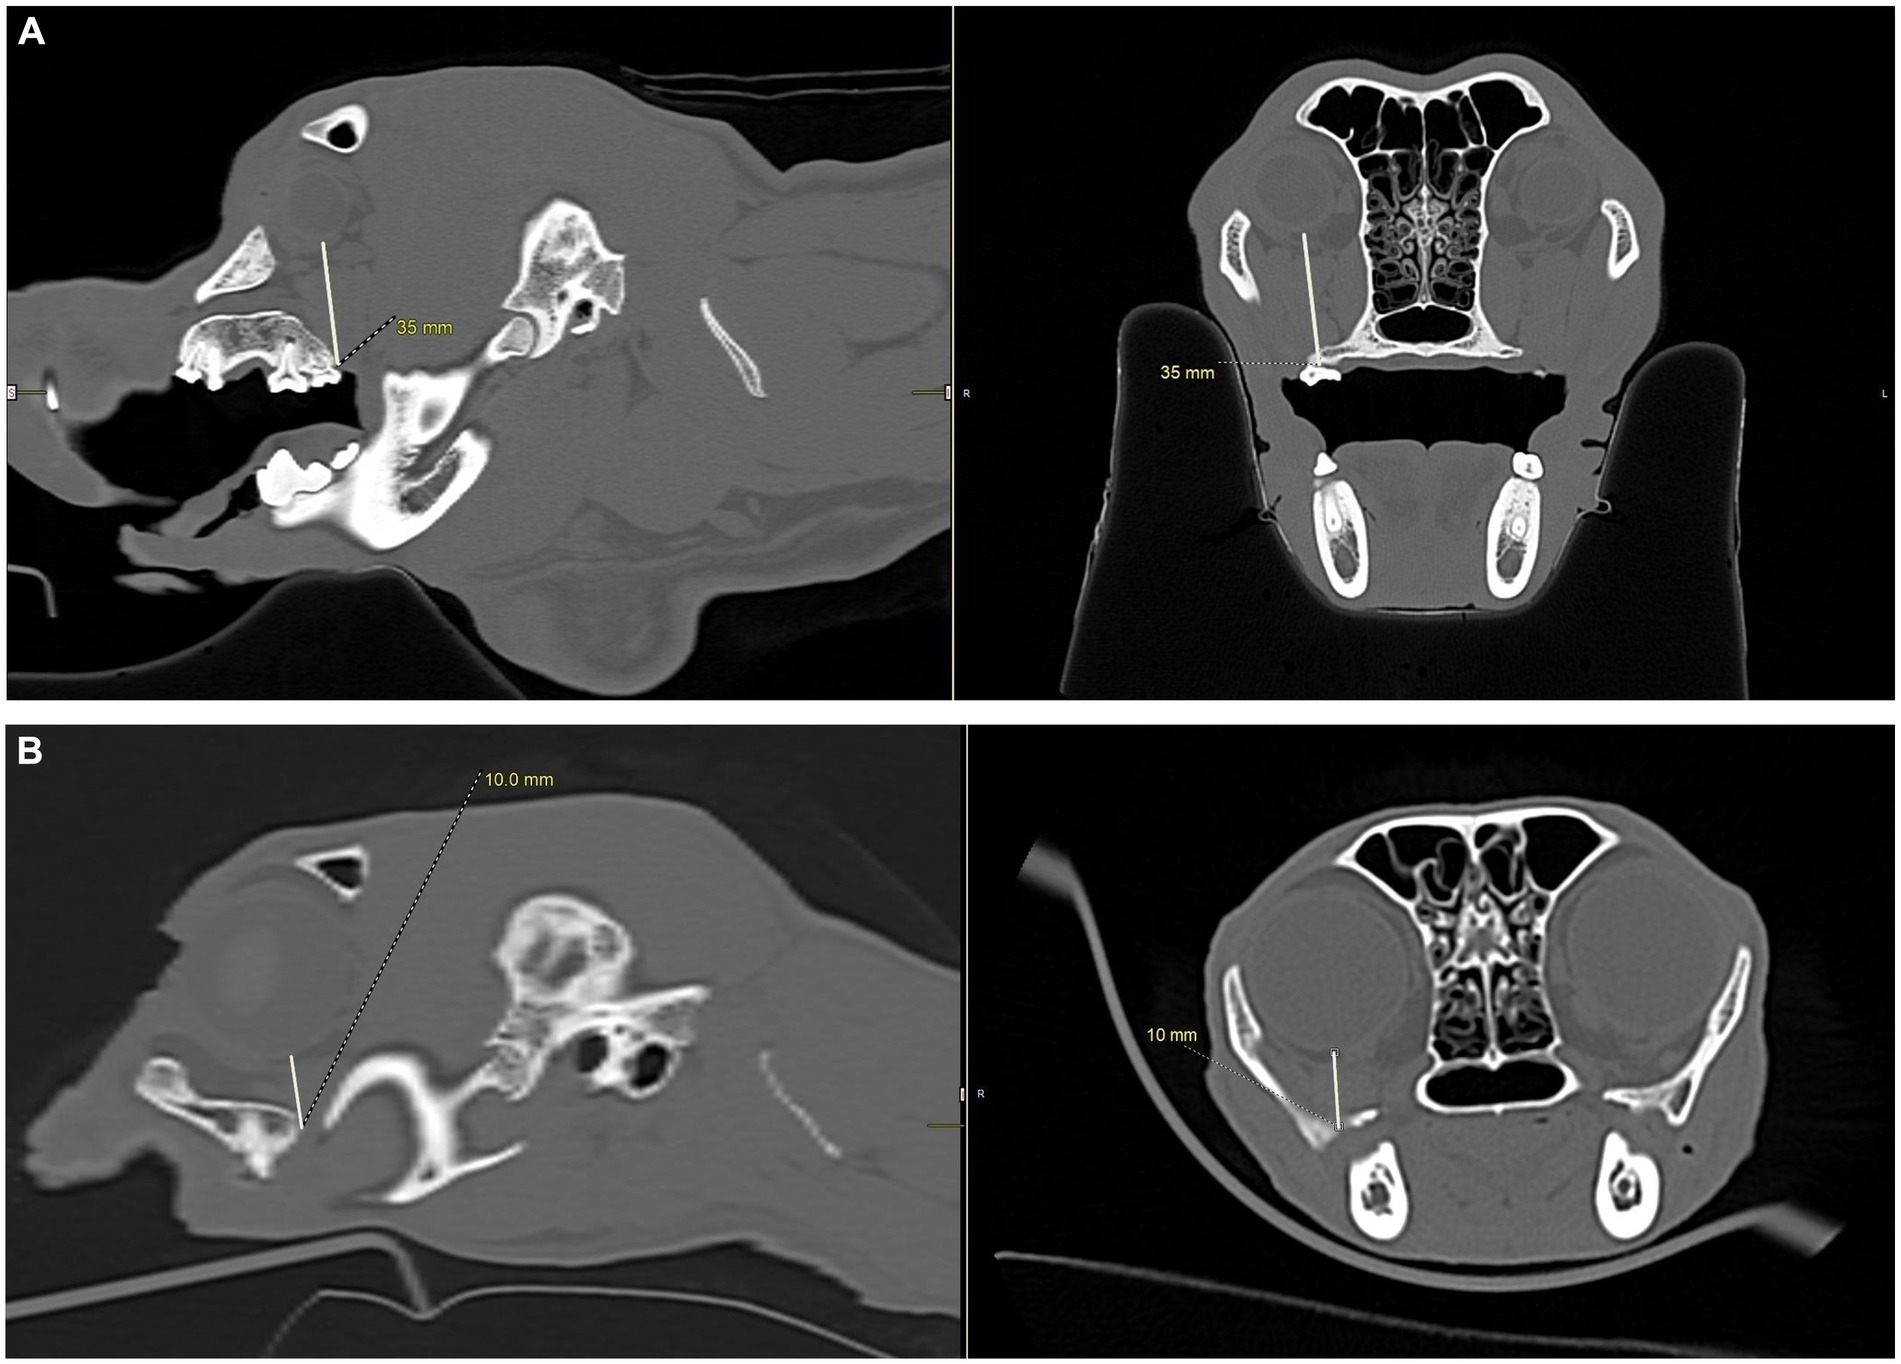

CT scan images showing measurements of structures within dog and cat skulls. Panel A displays measurements of 35 millimeters in both sagittal and transverse views showing a measurement from the hard palate to the eye in a dog skull. Panel B reveals a reduced measurement of 10 millimeters in saggital and transverse views showing a measurement from the hard palate to the eye in a cat skull. The images exhibit detailed bone and tissue structures.

Figure 6. CT images showing measurements, in millimeters, from the caudal palate, immediately caudal to the maxillary second molar tooth in dogs and the maxillary first molar tooth in cats, to the closest surface of the globe. (A) Sagittal (left) and transverse (right) views of a dog skull showing the measurements taken immediately caudal to the right maxillary second molar tooth to the closest surface of the globe. (B) Sagittal (left) and transverse (right) views of a cat skull showing the measurements taken immediately caudal to the right maxillary first molar tooth to the closest surface of the globe.

To simulate accidental globe puncture during the intraoral caudal maxillary nerve block, measurements were taken from the caudal border of the palate, immediately caudal to the maxillary second molar tooth in dogs and maxillary first molar tooth in cats, to the closest surface of the globe (palate-to-globe) using sagittal and transverse views (Figures 10C,D). In dogs and cats with a last mandibular molar tooth, the distance from the distal crown surface of the last mandibular molar tooth to the first CT slice with an open mandibular foramen was recorded using the transverse view (Figures 11AD). Accurate distance measurements from the last mandibular molar tooth to the mandibular foramen were not possible on the sagittal view due to the angulation of the mandible. Root length determination for the distal buccal root of the maxillary first molar tooth in the dogs was measured from the cementoenamel junction to the root apex (Figure 12A). Root length determination for the distal buccal root of the maxillary second molar tooth was measured from the horizontal pulp horn to the root apex (Figure 12B). The cementoenamel junction was not as discernible on the maxillary second molar tooth of the dog, so the horizontal pulp horn was used instead. If the distal buccal root length of the maxillary second molar tooth was not visible on a single transverse slice, then the palatal root was measured instead using the technique described in the previous sentence (Figure 12C). All measurements were collected and recorded separately for the left and right sides. Results were grouped and placed in tables according to their use in clinical practice. Minimum and mean distance values of the infraorbital foramen-to-globe, left and right maxillary first and second molar tooth root apex-to-globe, and palate-to-globe distance values in dogs were grouped (Table 1). Minimum and mean infraorbital foramen-to-globe, left and right maxillary fourth premolar tooth root apex-to-globe, and palate-to-globe distance values in cats were grouped (Table 2). Values ≤2.8 mm were highlighted in gray. Minimum, mean, and standard deviation for infraorbital canal length, infraorbital foramen width and height, and percent of animals with a bifurcation of the infraorbital canal for all cats and dogs were grouped (Table 3). Mean distances from the distal crown surface of the last mandibular molar tooth to the mandibular foramen, and palate-to-maxillary foramen for all dogs and cats were grouped (Table 4). The percentage of distal buccal roots fused with the palatal root, and root length measurements for the maxillary first and second molar teeth in dogs were grouped (Table 5). The percentage of teeth in which the globe was centered over was determined for each body weight and skull type (Table 6), with the first and second highest percentage points highlighted in gray. Results of the most likely position of the eye were recorded for 28 dolichocephalic dogs ≤10 kg, 43 dolichocephalic dogs ≥11 kg, 56 mesocephalic dogs ≤5 kg, 56 mesocephalic dogs of 6–10 kg, 64 mesocephalic dogs ≥11 kg, 62 brachycephalic dogs ≤10 kg, and 62 brachycephalic dogs ≥11 kg (Table 6). Results were recorded for 62 MCat and 16 BCat cat eyes (Table 6). Mean, median, mode, minimum, maximum, and standard deviation of the globe diameter for all cats and dogs were grouped (Table 7). Results were calculated for 28 dolichocephalic dogs ≤10 kg, 43 dolichocephalic dogs ≥11 kg, 63 mesocephalic dogs ≤5 kg, 60 mesocephalic dogs of 6–10 kg, 64 mesocephalic dogs ≥11 kg, 62 brachycephalic dogs ≤10 kg dog eyes, 62 brachycephalic dogs ≥11 kg dog eyes, and 62 MCat and 16 BCat cat eyes. Minimum and mean infraorbital canal length, infraorbital foramen-to-globe, and recommended safe catheter or needle insertion length, for the infraorbital and modified infraorbital approach to the maxillary nerve blocks, were calculated for all cats and dogs (Table 8). All dogs below the mean infraorbital length standard deviation value for infraorbital canal length were considered “extreme brachycephalic” by the authors and included French bulldogs and pugs (four animals in total). The authors observed that French bulldogs, pugs, and Boston terriers had similarly shorter infraorbital canal mean lengths of 2–9 mm, across both ≤10 kg and ≥11 kg brachycephalic weight categories. Boston terriers, French bulldogs, and pugs were pooled together in a group labeled “extreme brachycephalic” for a total of 20 animals (14 French bulldogs, 2 pugs, and 4 Boston terriers), and their values are reported in the second-to-last row of Table 8. Minimum and mean infraorbital canal length and infraorbital foramen-to-globe length distances were recalculated for the brachycephalic dogs ≥11 kg dog group, with extreme brachycephalic dogs removed, to reflect a more accurate representation of the infraorbital canal lengths in these groups (Table 8). Groups where both the minimum infraorbital canal length and infraorbital foramen-to-globe distances were less than 10 mm were highlighted in gray to indicate that extreme caution should be used.